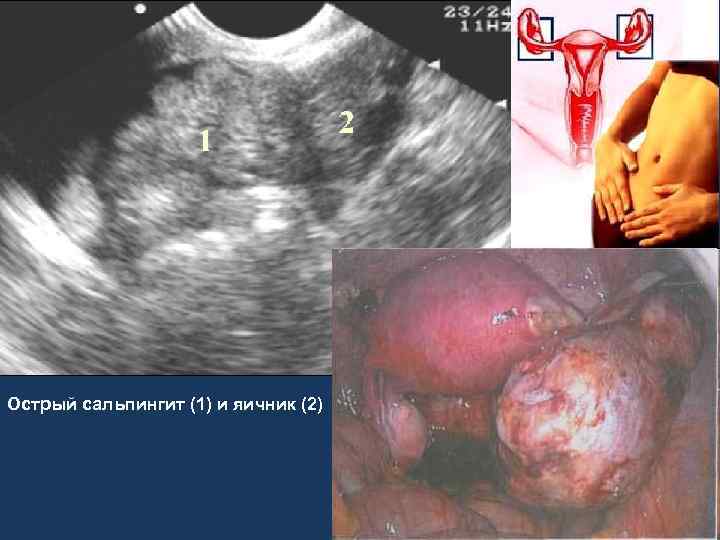

Острый аднексит • Боль внизу живота • Клиника развивается на фоне предшествующих гинекологических заболеваний. • Общее состояние больных, как правило, не нарушено, они обычно активны (в случае отсутствия деструктивного процесса). • Симптомы раздражения брюшины незначительны. • Диагностика: клиническое наблюдение, гинекологический осмотр, УЗИ, при неэффективности – лапароскопия.

Острый сальпингит (1) и яичник (2)